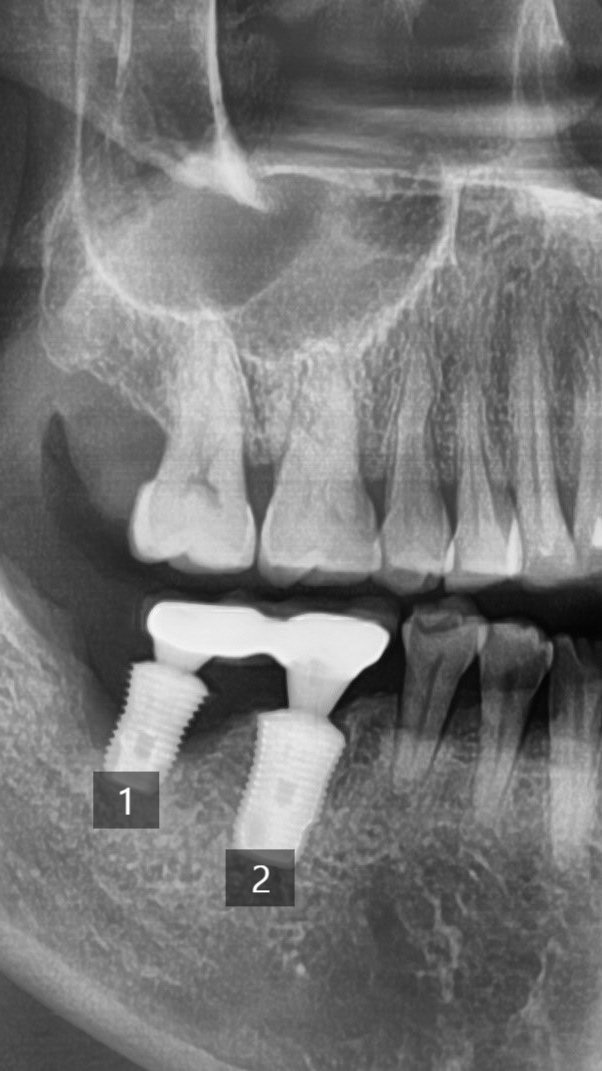

아래쪽 임플란트가 흔들려서 뽑기를 원하셨습니다.

사진에 1번이라고 표시된 인프란트는 뼈가 많이 녹아서 흔들리는 것이고

2번의 임프란트는 엑스레이상에 뼈가 많이는 녹은 것처럼 보이지 않지만

실제로 수술을 해보니 2번의 임플란트 중간에 어버트먼트를 위한 나사가 파절되어 임플란트 머리가 흔들렸습니다.